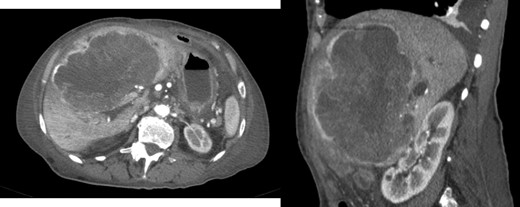

A 26-year-old woman, with past medical history of removal of hemangiopericytoma of the right leg, was referred to our Hepatobiliary Unit due to a liver tumor that was discovered on abdominal-pelvic computed tomography (CT) scan, performed after complaints of epigastric pain. CT scan (Fig. 1) showed a voluminous, heterogeneous, hypervascular mass, occupying segments 4, 5 and 8, with 19 cm in diameter, as well as suspicious lesion on left iliac bone suggestive of solitary fibrous tumor metastasis.

Abdomino-pelvic computed tomography (AP-CT) – voluminous heterogeneous liver mass in segments 4, 5 and 8 with 19 cm in diameter.